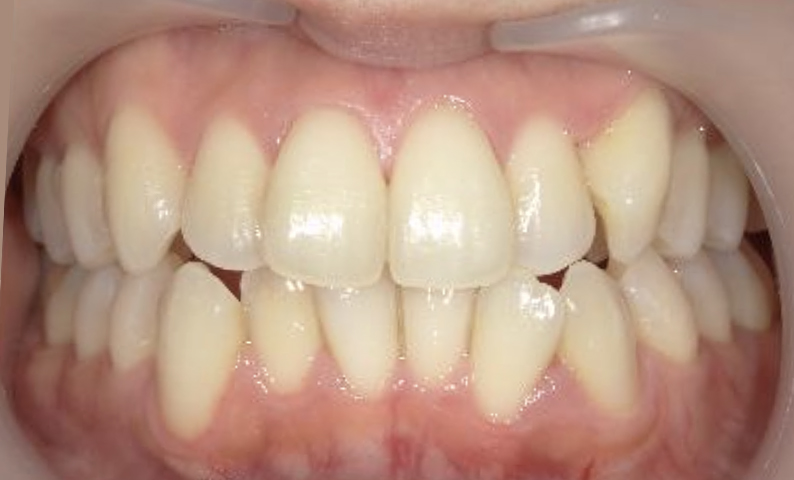

症例_025 上下顎の部分矯正

治療期間:13ヶ月金額:51万円+税女性前歯のガタガタ出っ歯